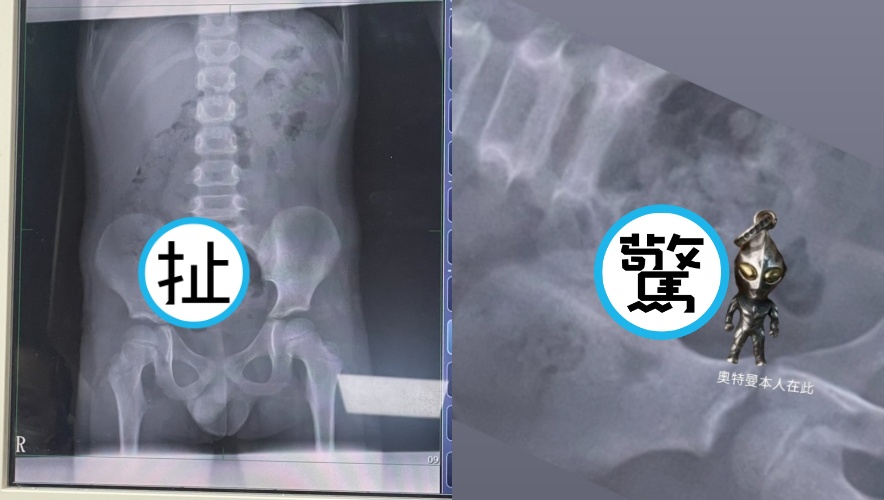

原PO更把吊飾與X光影像放在一起對照,並標註「奧特曼本人在此」,讓不少網友笑瘋,留言直呼:「這X光片可以帶回家裱框嗎?感覺很酷欸🤣」「大出來是不是變成奧德賽」「奧特曼已經快走到出口了,離開洞口會ㄎㄧㄤ一聲」「預產期是兩天後」「奧特曼:你相信光嗎」「如果是博愛醫院的話 我今天就在旁邊 聽到奧特曼也不小心笑出來….🤣」